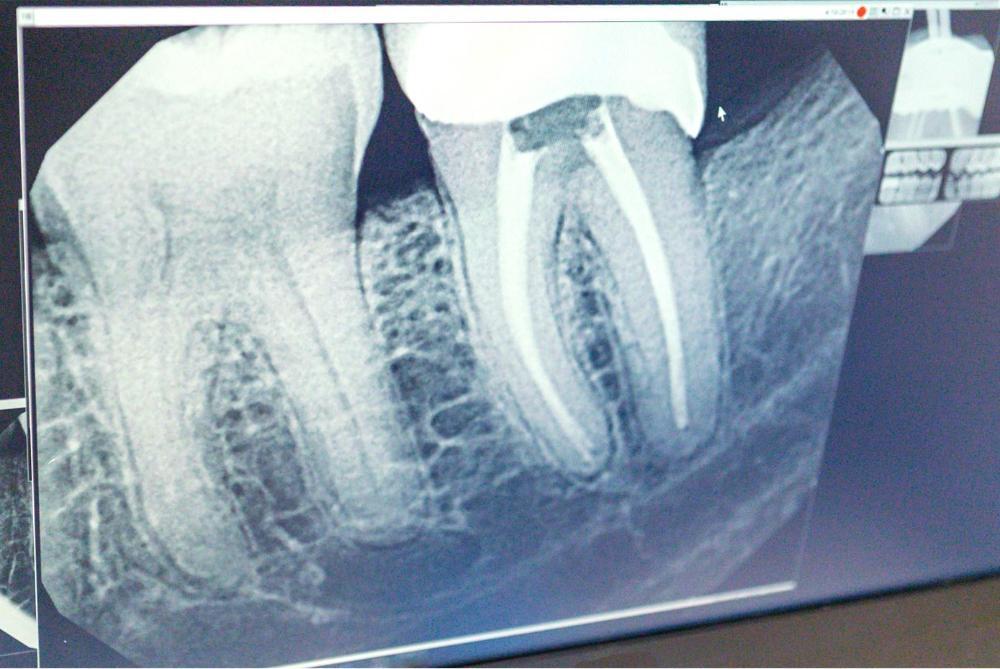

When you arrive at our office, Dr. Haag will perform a visual inspection and take x-rays to determine if the root canal is infected. If it is, a root canal treatment is in order.

First, we use a local anesthetic to numb the tooth and surrounding area. The infected nerve and pulp are then gently removed from the tooth using precision instruments. After the tooth is completely cleaned out, medication may be placed inside the tooth to destroy any remaining bacteria.

Once we are satisfied that there is no longer any sign of infection, we fill the tooth using a special sealant. A crown is placed over the exterior of the tooth to restore the functioning of the tooth and prevent further damage.